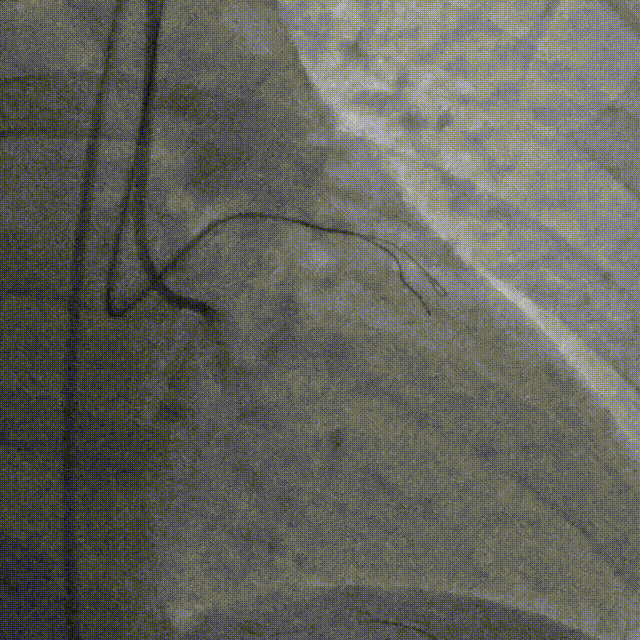

RCA中段扩张后出现夹层,植入DES。